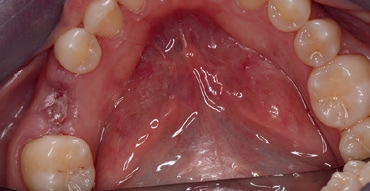

Eine 36-jährige Patientin stellte sich mir mit einem gefüllten Milchzahn an Position 85 vor. Der Zahn war aufgrund einer Sekundärkaries mit folglicher Pulpanekrose nicht erhaltungswürdig und sollte aufgrund der Nichtanlage des Zahnes 45 durch ein Implantat ersetzt werden (Abb. 1a und b). Zielsetzung war eine Sofortimplantation sowie die Sofortversorgung des Implantats. Eine andere Möglichkeit wäre eine kieferorthopädische Behandlung zum teilweisen oder vollständigen Lückenschluss gewesen oder alternativ die klassische Versorgung mittels einer 3-gliedrigen Brücke, jedoch bei unversehrten Pfeilerzähnen. Beide Konzepte schieden patientenseitig aus.

Die intraorale Röntgenaufnahme zeigte die übliche 2-wurzelige Konfiguration des Milchmolaren, apikal das Foramen mentale sowie gering ausgeprägte trabekuläre Strukturen der regionalen Spongiosa aufgrund der kurzen Wurzelkonfiguration (Abb. 2). Eine geführte Implantation, für deren Umsetzung ein DVT angefertigt wurde (Orthophos XG 3D), bot hier den Vorteil einer sicheren Führung ohne Richtungsablenkung durch die bestehenden Alveolen sowie der optimalen Ausnutzung des vorhandenen Raumangebots, um maximale Stabilität zu erreichen. Aufgrund der größeren mesiodistalen Breite des Zahnes 85 im Vergleich zu üblichen Prämolaren orientierte ich mich bei der prothetischen Planung am vorhandenen Milchmolaren.